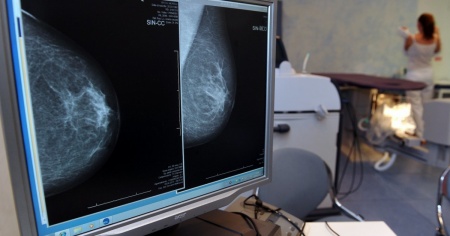

LUGANO - È boom di operazioni per un tumore al seno. Le sale operatorie ticinesi sono piene. Come mai prima d'ora. Francesco Meani, responsabile clinico del Centro di Senologia della Svizzera italiana (EOC), con sede principale a Lugano, conferma il fenomeno. «Solitamente una donna per essere operata deve aspettare circa due settimane. Ora tra le quattro e le cinque».

«Personalmente lo introdurrei annuale e dai 40 anni. È vero che i costi di prevenzione aumentano. Ma si risparmia poi con le cure. Penso che la risposta starà nella personalizzazione dei controlli, in base al rischio di ciascun paziente. Sono circa 350 i nuovi casi all'anno in Ticino. Mentre in Svizzera sono circa 5.000. Più del 90% dei casi può essere curato. Però ci vuole una diagnosi precoce».